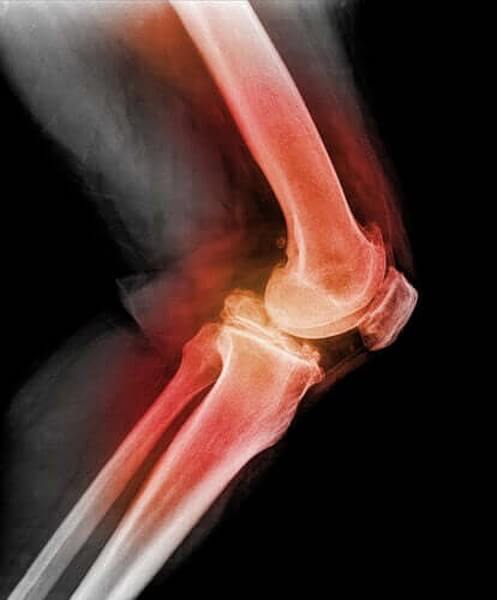

For at diagnosticere patellaluksation (når knæskallen er gået af led) vil lægen røre ved knæskallen og bøje benet, samtidig med at han eller hun bevæger det i forskellige retninger. Ved at anvende røntgenbilleder, MR-scanninger eller CT-scanninger kan lægen se billeder af den forskudte knæskal samt andre knæskader.